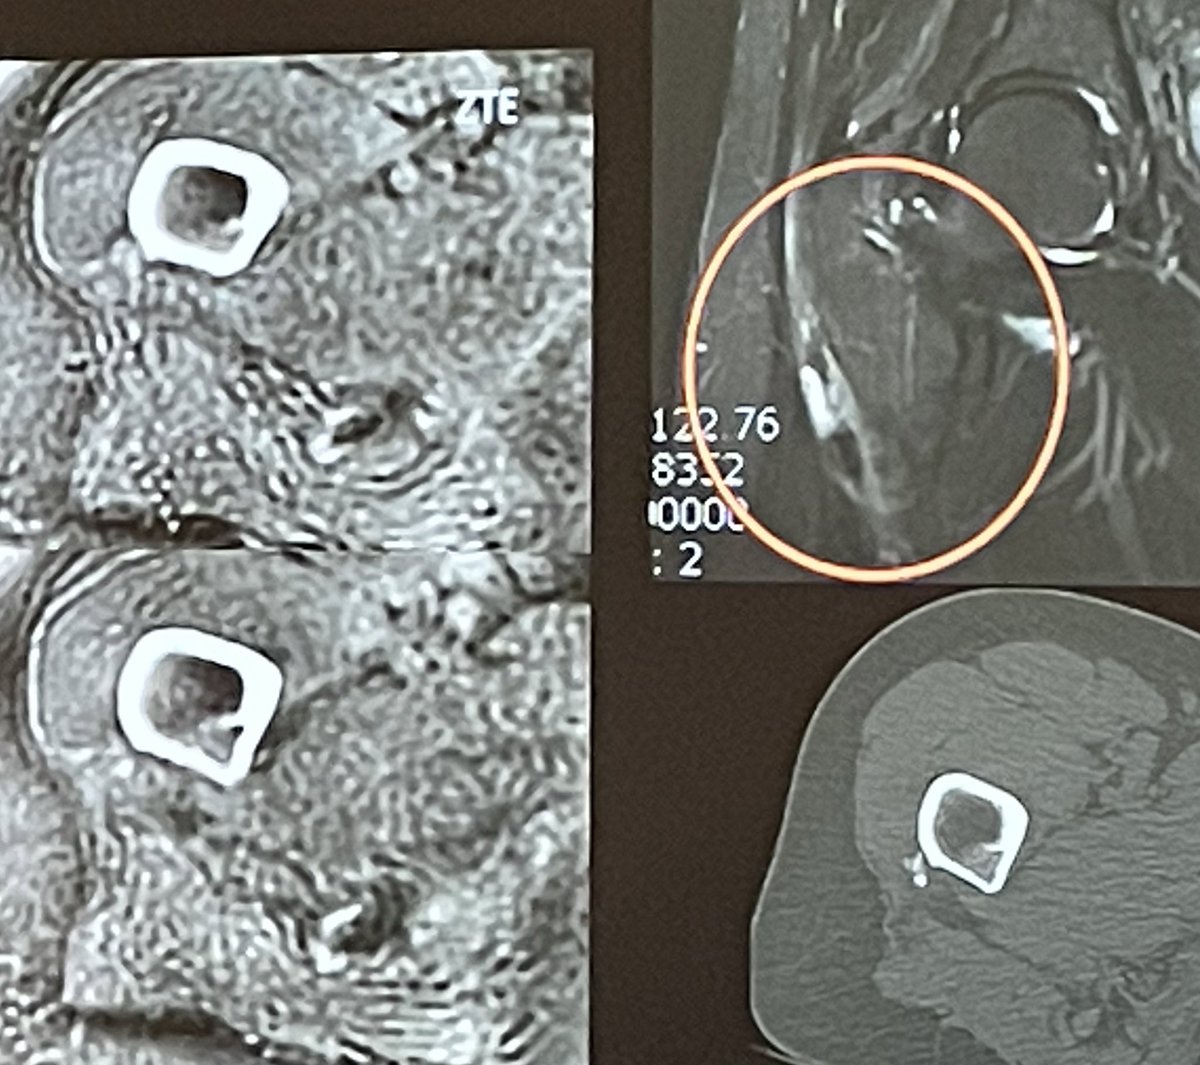

Dr Amine Korchi (@aminekorchimd) 's Twitter Profile Photo

MRI ZTE (Zero TE) sequence is a CT-like image & improves the diagnosis in certain situations without adding a CT : - Lumbar pain of adolescents -> isthmic lysis - Joint in the context of a trauma -> fracture - Extensive unexplained edema -> calcification

MRI ZTE (Zero TE) sequence is a CT-like image & improves the diagnosis in certain situations without adding a CT :

- Lumbar pain of adolescents

-> isthmic lysis

- Joint in the context of a trauma

-> fracture

- Extensive unexplained edema

-> calcification